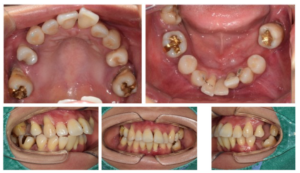

오늘 소개해 드릴

환자분께서는

30대 여성분으로

상실된 치아도 많고

흔들리는 치아도 많으시다며

전체적인 치료를 위해

내원해 주셨는데요.

치료기간: 24.07.24 ~ 25.11.20

먼저 구강 내를

확인해 보았더니

다수 치아의 상실로 인해

치아의 배열이 흐트러져 있고,

잔존 치아들도

동요도가 심한 상태였는데요.